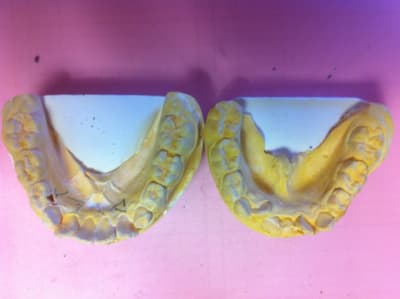

Img 3218 l9hvjz - Eugenol

Img 3610 pmoxur - Eugenol

01 ukhwbq - Eugenol

Je ne cherche pas à polémiquer, je pose simplement la question :

Tu penses arriver à traiter des cas comme ceux là, avec des gouttières ?

P.S.: la faiblesse des gouttières est la correction des rotations